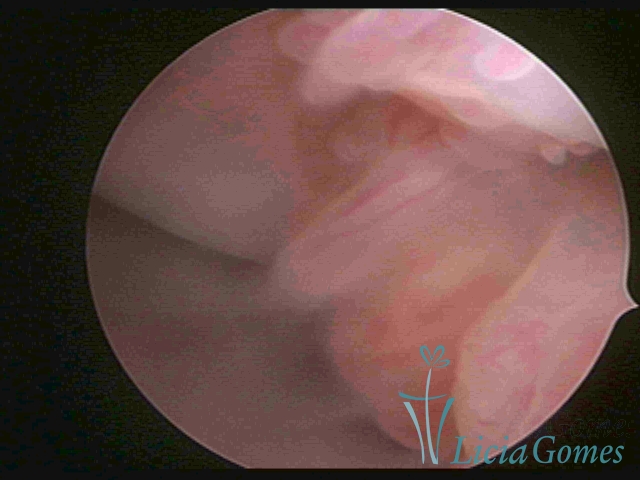

ENDOCERVICAL POLYPS

Benign tumors resulting from the reactive focal proliferation to inflammatory processes or hyperestrogenism situations, which may be sessile (with a large implantation) or stalked.